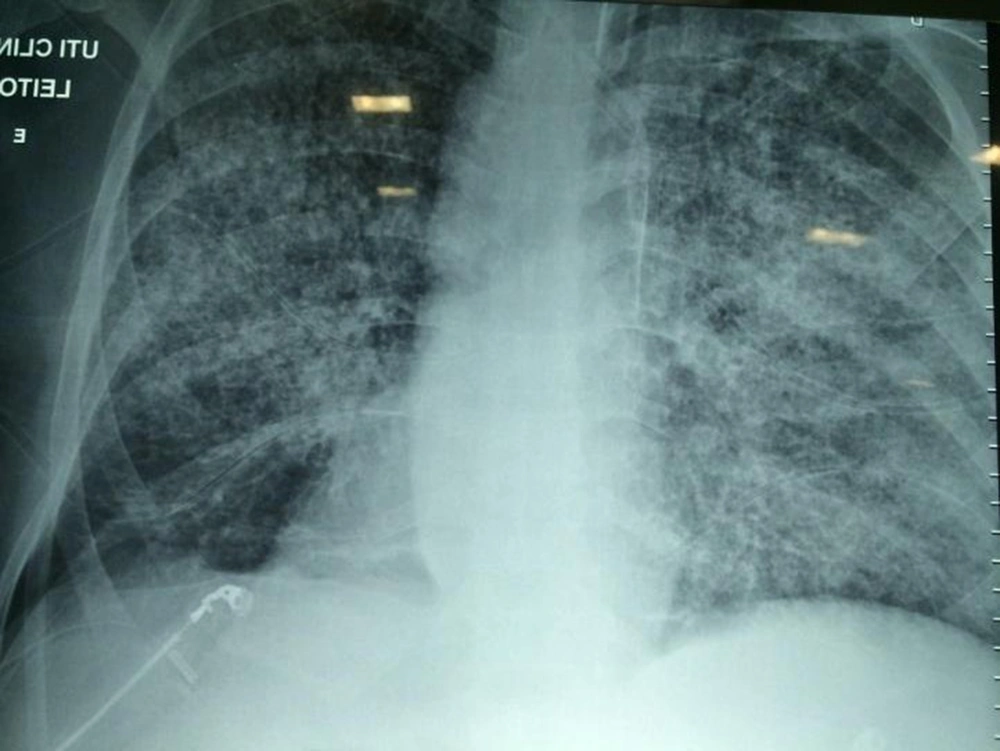

On the third day of intensive care, the patient developed respiratory failure, disorientation, and abdominal petechiae (Figure 2), requiring mechanical ventilation, in addition to vasoactive drugs, with suspected sepsis. A chest X-ray showed a worsening of the pulmonary infiltrate (Figure 2). On the fifth day of intensive care, hemodialysis therapy was indicated.

Disseminated petechial lesions associated with acute respiratory distress syndrome corroborated the diagnosis of disseminated strongyloidiasis. As there was no clinical improvement with oral treatment, a parenteral veterinary formulation of ivermectin (0.2 mg/kg/day) was initiated for 4 days.